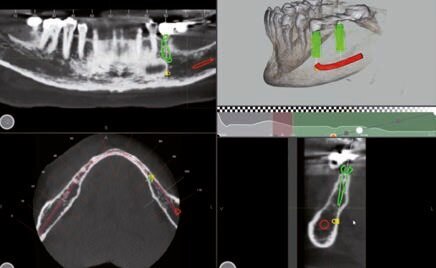

Fig. 2 - Misurazioni in sede 35.

Dopo aver valutato con la paziente tutti i pro e i contro abbiamo deciso di prediligere la scelta dei REX PiezoImplant. È stata eseguita un’impronta digitale che è stata accoppiata tramite il software di progettazione all’esame radiografico tridimensionale. Sono stati scelti due impianti REX PiezoImplant 1,8 x 11. L’impronta digitale della situazione pre-intervento della paziente ci ha permesso di utilizzare quest’ultima (come ceratura diagnostica) per programmare il posizionamento implantare in modo protesicamente guidato. La pianificazione software della fase chirurgica e l’utilizzo di una guida per il corretto posizionamento dell’impianto “asse implanto- protesico”, ci hanno permesso non solo di ottenere il posizionamento implantare nel rispetto dello spessore osseo disponibile “asse anatomico” ma anche di ricercare la migliore soluzione protesica avvitata, “asse protesico”, per una sensibile riduzione del rischio di errore. È stata creata una dima chirurgica che ci ha permesso di riportare nel cavo orale la programmazione dell’inserimento implantare che avevamo pianificato virtualmente. La metodica Rex permette di utilizzare una slitta che prevede una chirurgia guidata con sistema Pilot utilizzando l’inserto W2. Sono state raccordate le due preparazioni e le abbiamo estese con l’inserto OT7S3 che ci ha permesso di ottenere una maggiore elasticità ossea.